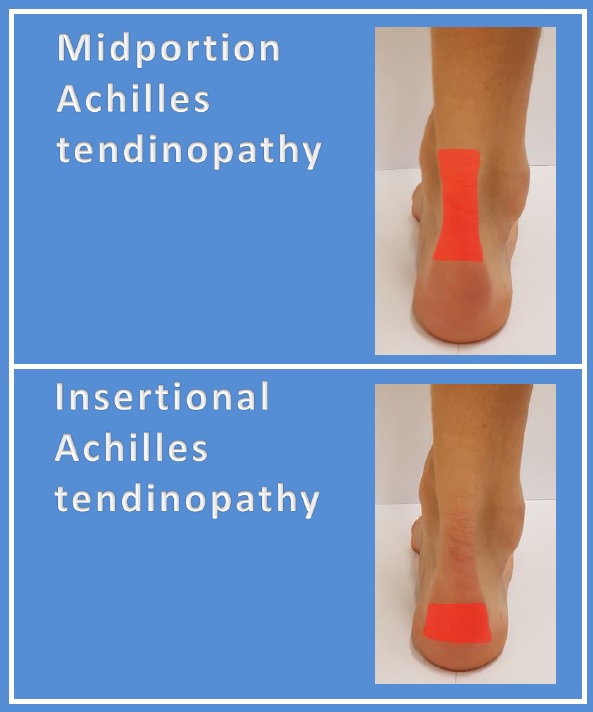

💥𝐀𝐜𝐡𝐢𝐥𝐥𝐞𝐬 𝐓𝐞𝐧𝐝𝐢𝐧𝐨𝐩𝐚𝐭𝐡𝐲💥 ——— 👣Achilles tendinopathy describes a …

What is Achilles Tendinopathy? – Insoles and Orthotics – Healthy Step

Achilles Tendinopathy (Tendinitis and Tendinosis) – Complete Feet …

Achilles Tendinopathy | Mr Daniel Goldbloom | Melbourne

Insertional Tendinitis Massage Treatment in the Achilles Tendon